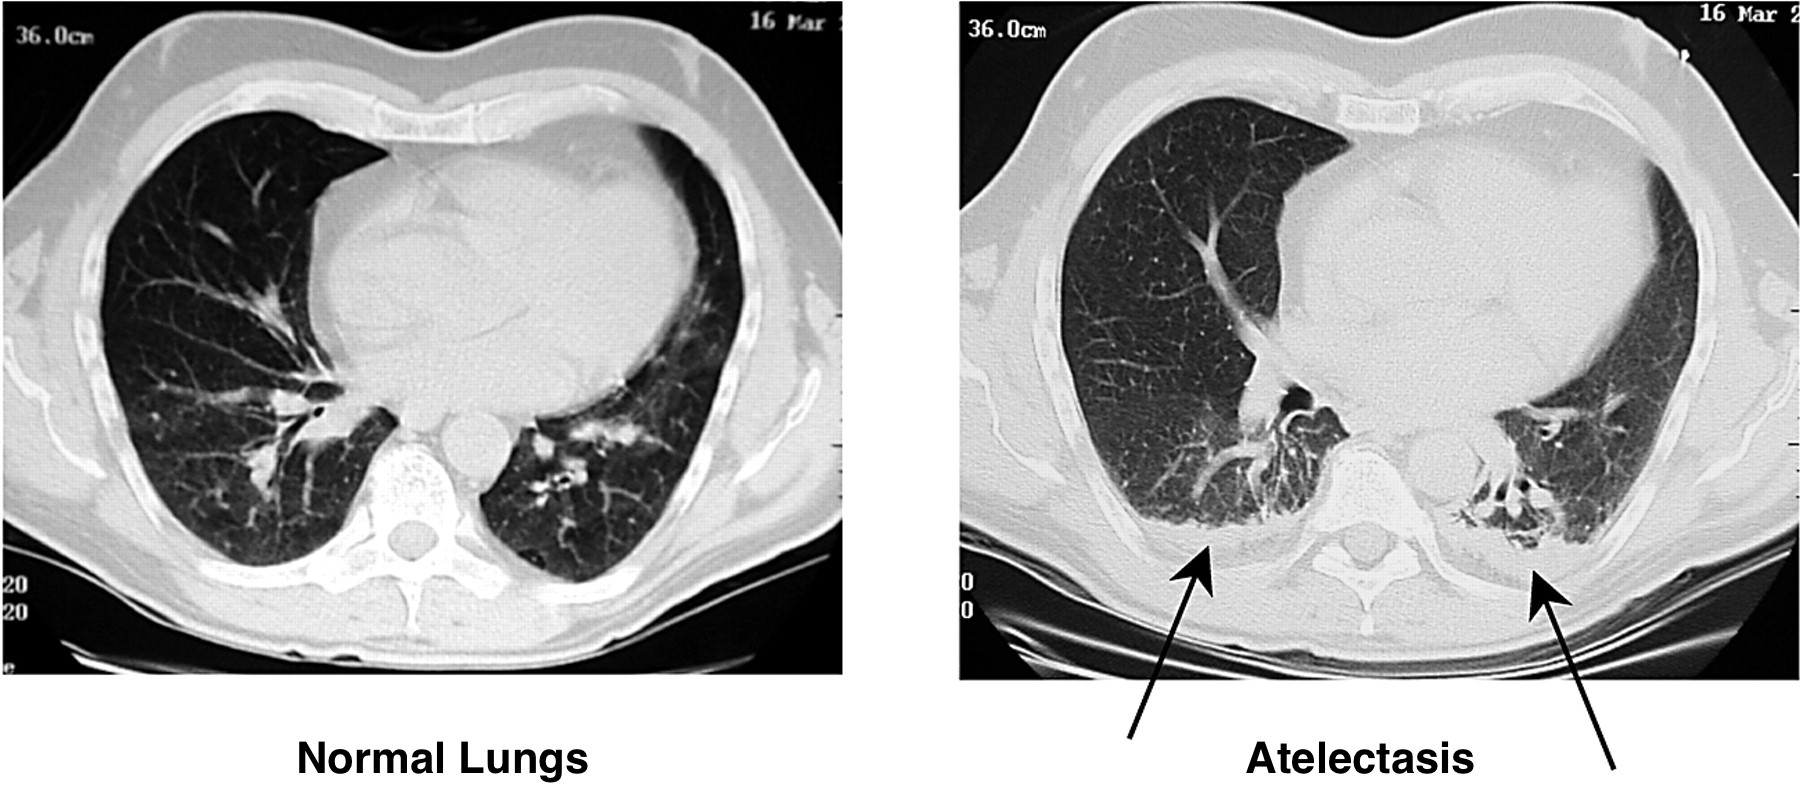

COMPUTIRIZED TOMOGRAPHY (CT-SCAN)

Atelectasis can also be visualized on a CT scan

Some key features to keep in mind for the appearance of atelectasis on a CT-scan are:

- Presence of signal: fundamentally the collapse of this lung parenchyma will appear over a portion of the lung field. On a CT- scan this will show up as an increased signal.